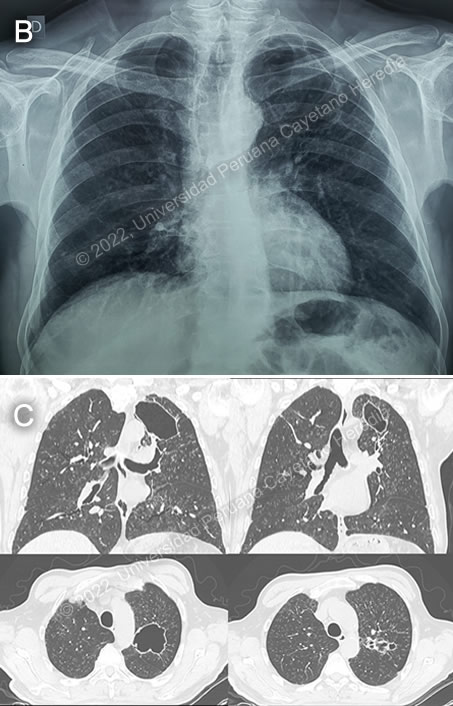

The following patient was seen in the inpatient ward of Cayetano Heredia Hospital in Lima by the 2022 Gorgas Course participants. ![]() ![]() History: A 60-year-old male patient presented with a 3-year history of cough, occasional hemoptysis, and worsening dysphonia. Five months before admission, he became aphonic and reported odynophagia and progressive dysphagia for liquids then solids. 4 months before admission, a laryngoscopy at a private hospital found granular changes in his vocal cords, but he did not receive any treatment. One and a half months before admission, repeat laryngoscopy at our hospital [Video A], found central granulomatous lesions in the vocal cords with incomplete closure of cords and preserved motility. He did not recall having fever throughout the course of the disease; but reported weight loss of 15 kg. Epidemiology: He was born in La Oroya, in the central highlands in Peru. Thirty years ago, he spent six years working as a farmer in Oxapampa, in the central jungle, harvesting coffee and other fruits. He has lived in Lima for thirty years, where he worked in public transport for 18 years, and currently works as a clerk in a hotel. No known TB contacts, no risky sexual or social behaviors. Physical Examination: T: 36.9°C, BP 140/90 mmHg, HR 82 bpm, RR 18 rpm, SatO2 96% on room air. Laboratory Results: Hb 13.4, Leu 14 (bands 0%, seg 91.2%, eos 0%, baso 0.1%, mono 2.6%, lymph 5.3%), Plt 391 000; PT 13.8, INR 1.01; BUN 28, Cr 0.59, Na 137, K 4.32, Cl 92; ALT 15, AST 19, LDH 149. PPD was 15 mm. Imaging: Chest X ray [Image B] showed a cavitary lesion in the left upper lung field. Thoracic CT scan [Image C] showed centrilobular nodules in a tree pattern, diffusely distributed but predominantly in superior lobes, and tubular bronchiectasis in the right basal posterior segment and left apical segment; the biggest one 50x59mm. Neck CT showed pathological thickening of both aryepiglottic folds (predominantly right) with irregular contrast enhancement, and a 7mm lymph node in left group III suspicious for lymphadenopathy.

Diagnosis: Paracoccidioides braziliensis, chronic multifocal form.

![]() Discussion: On biopsy of the larynx, a dense chronic inflammatory reaction with granuloma formation with yeast forms of varying sizes was observed [Image D]. Subsequent sputum samples tested positive for yeast cells in KOH preps [Image E]. Sputum AFB was negative x3, GeneXpert TB in sputum was negative. HIV testing was negative. COVID-19 testing was negative as well. The chronic form of paracoccidioidomycosis most often involves pulmonary disease with oral mucosal involvement as a frequent complication [Gorgas Case 2004-05]. The differential diagnosis for the lung disease includes TB, histoplasmosis, lymphoma, cancer and cryptococcosis. Tuberculosis was the leading diagnosis in this case, but extensive investigations revealed negative results. The findings on the biopsy and cultures ruled-out other conditions. The typical radiographic pattern of paracoccidioidomycosis is with bilateral mixed infiltrates (alveolar and interstitial), mainly located in the middle and lower lobes. Interstitial lesions may have miliary (as in this case), nodular or fibronodular patterns. Other patterns observed in these patients are hilar and mediastinal lymph node enlargement, cavities, and calcified lesions. Extrapulmonary disease is found in over 70% of cases and may involve skin, mucous membranes, lymph nodes, adrenals, abdominal organs and CNS (in 9-25%). The most notable clinical findings in this patient are the long latency period from possible infection to development of symptoms; lack of oral involvement; presence of cavitary lesions and the prominent laryngeal involvement. A long latent period is characteristic of paracoccidioidomycosis, reports of decades of latency among expatriates are well known [Mycoses. 2003;46(9-10):407-11]. Cavitary lesions are not common but have been reported, unilateral or bilateral cavities may occur. In all these cases tuberculosis and other conditions were ruled out [Eur J Radiol 2018]. The larynx may be involved either by the hematogenous route or from extension of lesions in the oral cavity, and its involvement was recognized early on by the discoverers of the disease back in 1908. The absence of oral lesions in this case argues against extension from the oral cavity and favors hematogenous dissemination. Laryngeal involvement is reported in 22-43% of patients [Medical Mycology 2006;44:219-25]. The whole larynx may be involved, including the vocal cords, epiglottis and infraglottic [Arch Otolaryngol Head Neck Surg 1999;125:1375-8]. It classically presents in middle-aged males with dysphonia, dyspnea and cough. Laryngeal examination reveals ulcerative and vegetative lesions. The accurate diagnosis requires obtaining tissue to be sent for culture and histopathology. Classical pathological findings include a dense inflammatory reaction, multinucleated giant cells and yeast cells of different sizes with multiple peripheral budding, as in this case. The differential diagnosis is broad and includes tuberculosis, leishmaniasis, histoplasmosis, actinomycosis, syphilis, sarcoidosis, cancer and vasculitis [Eur Arch Otorhinolaryngol 2008]. Important sequelae such as hoarseness, glottal and tracheal stenosis and dysphonia may occur. Treatment in addition to antifungals requires the use of steroids [Medical Mycology 2012]. Tracheal stenosis and asphyxia as a result of an intense inflammatory reaction induced by the release of antigens from the dying fungi during treatment with antifungals have been reported. Prednisone at 1 mg/kg or its equivalents is recommended for 10 days with progressive tapering over the next 4 weeks [Med Mycol 2012]. Some experts recommend starting steroids a few days before antifungal treatment to minimize obstructive complications. This recommendation is based on experience with laryngeal involvement in tuberculosis and leishmaniasis. There is no other indication for using systemic steroids in paracoccidioidomycosis. Our patient was started on dexamethasone 7 days prior to initiating oral itraconazole. The extensive laryngeal involvement and the high risk for airway obstruction argued against starting amphotericin B. Itraconazole is going to be offered for at least one year with serum drug level monitoring and clinical-microbiological follow-up. A new laryngoscopic examination will be performed after one month of therapy and subsequently based on clinical evolution. |